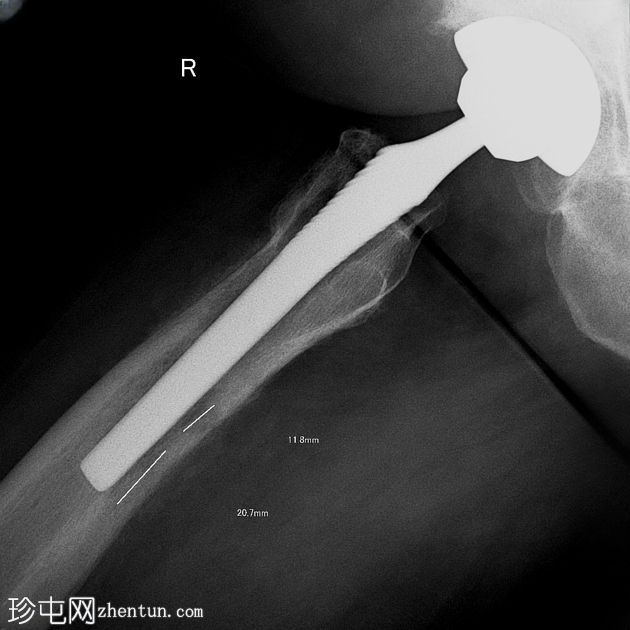

2.jpeg

正面

右侧股骨骨干近端1/3可见明显的骨皮质变形,并伴有环状骨膜反应。内侧和腹侧表面可见边界清晰的椭圆形透亮区,最大直径约1厘米和2厘米,为骨皮质渗透区。